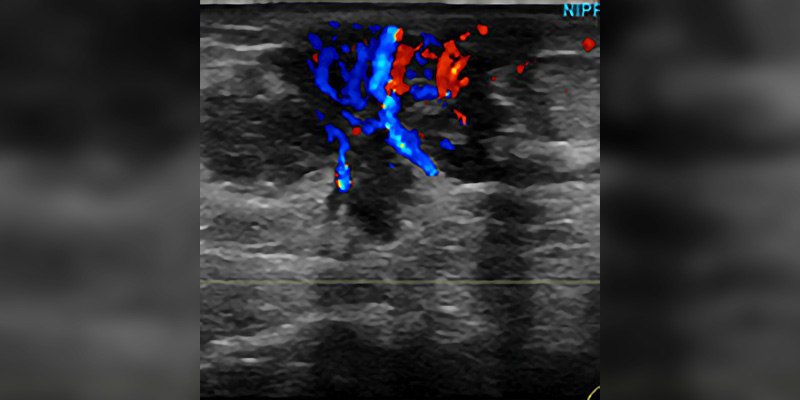

Breast Sonography Registry Review